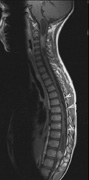

Intracranial leptomeningeal capillary vascular malformation (Figs. 21 and 22) is associated with seizures and contralateral neuromuscular weakness. Central nervous system involvement correlates highly with ipsilateral involvement of the V1 dermatome by a PWS.208,218

Fig. 22. Axial T2-weighted (a) and coronal T1-weighted (b) images of a 16-year-old boy with a port-wine lesion over the right side of his face. The right hemisphere is markedly atrophic and abnormal draining veins are seen within the right lateral ventricle (arrowheads). (c, d) The entire right hemisphere is covered by an enhancing pial angioma and the choroid plexi are enlarged. Enhancing retinal angiomas (arrows), typical of Sturge-Weber syndrome, are seen in (d).